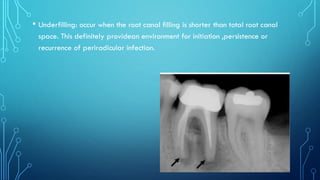

• Underfilling: occur when the root canal filling is shorter than total root canal

space. This definitely providean environment for initiation ,persistence or

recurrence of periradicular infection.